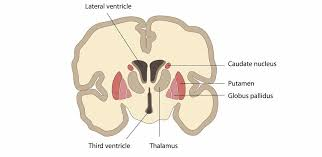

cerebral nuclei

deep regions of gray matter

diencephalon

relay station for most sensory and motor pathways, controls visceral activities

diencephalon structures

epithalamus, thalamus, hypothalamus

thalamus

2 halves; sensory impulses from all conscious senses converge on thalamus and synapse and one of its nuclei; made up of about a dozen nuclei

thalamus